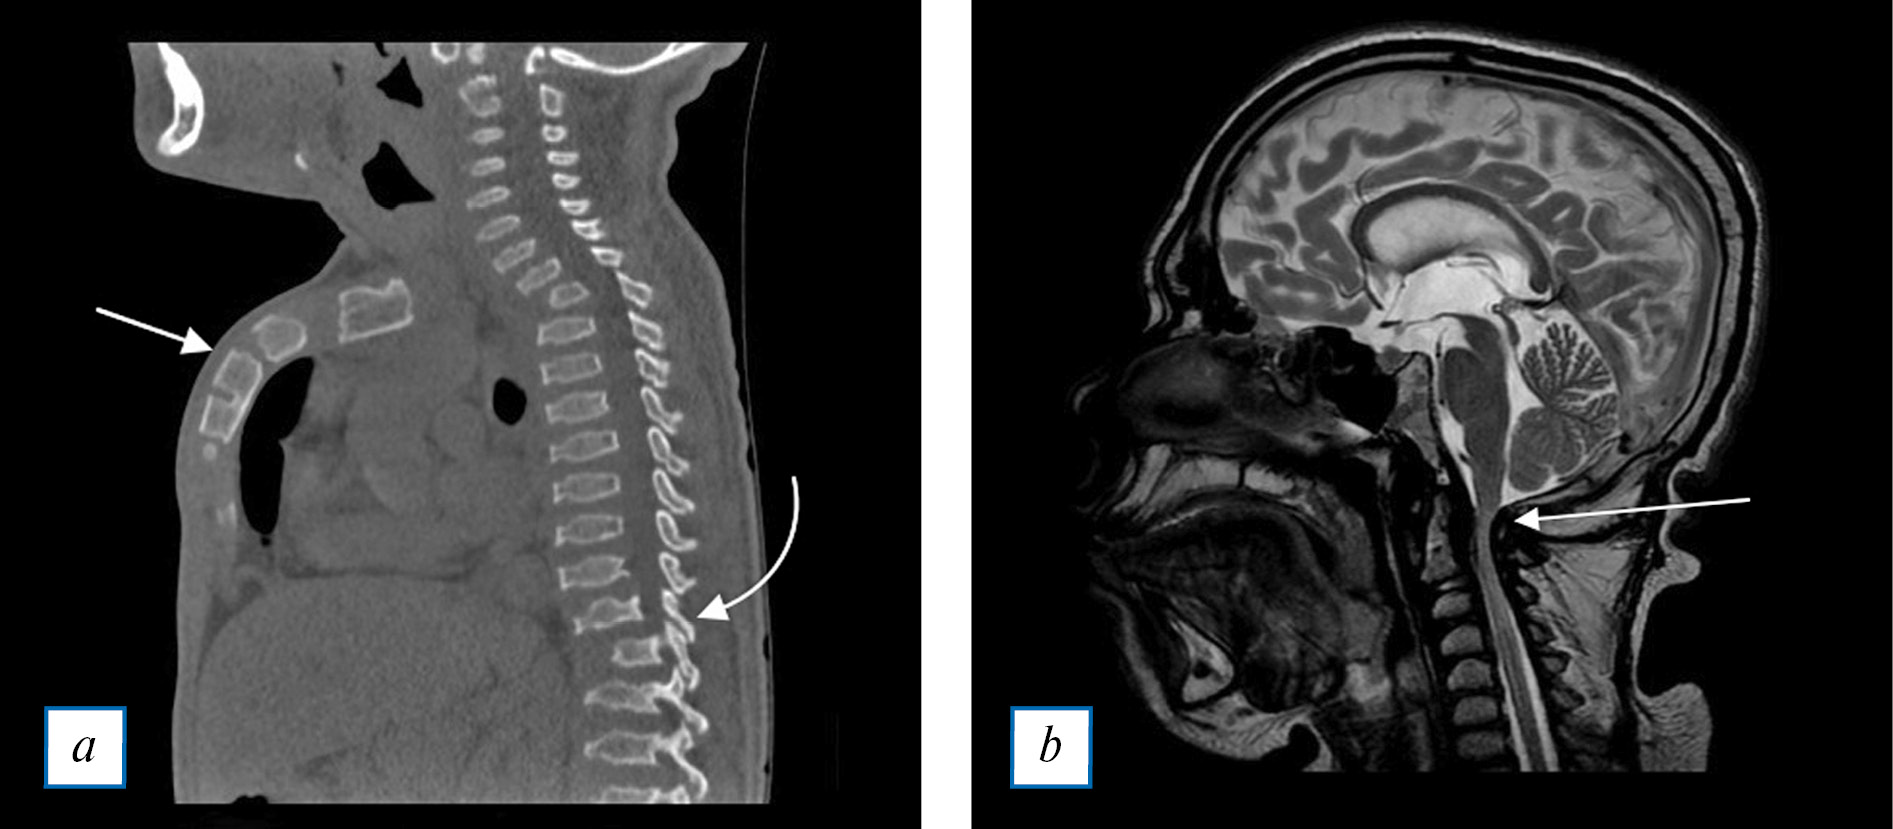

В позвоночнике характерной деформацией является платиспондилия, вогнутость заднего и заострение переднего контуров позвонков, клиновидная деформация позвонков (рис. 5, а). Изменения могут приводить к кифотической гиббусной деформации (gibbus — горб, остроугольное искривление позвоночника) и сколиозу. Поражаются и межпозвонковые диски с нарушением их структуры, снижением высоты; могут определяться циркулярные выпячивания и грыжи [17, 27].

Самым грозным осложнением дизостозов является стеноз позвоночного канала, который возникает в результате повышенной пролиферации костей основания черепа и С1-С2 позвонков, а также утолщения периодонтоидных мягких тканей (рис. 5, б) и базилярной инвагинации (вклинение в большое затылочное отверстие) [18].

Рис. 5. Дизостозы позвоночника: а (КТ в сагиттальной плоскости) — прямой стрелкой показано утолщение, укорочение и деформация грудины, изогнутой стрелкой — снижение высоты тел позвонков, деформация их контуров; b (МРТ Т2-ВИ в сагиттальной плоскости) — стрелкой показана область стеноза позвоночного канала, который вызван утолщением периодонтоидных мягких тканей.

Fig. 5. Spinal dysostosis: a (computer tomography of the vertebral column in the sagittal plane) — arrow: thickening, shortening and deformity of the sternum, curved arrow: flattening and deformation of vertebral bodies; b (MRI T2-WI in the sagittal plane) — arrow: the vertebral canal stenosis due to enlarged periodontoid soft tissue.